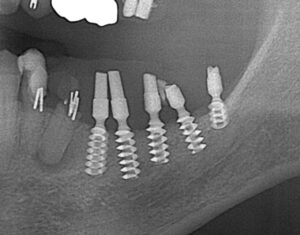

OGAインプラント

今ではほとんど見ないタイプのインプラントです。

私も当時このインプラントについて知識がなかったため、このインプラントを積極的に行われていた第一人者でもある先生にお話を伺いました。(現在は引退されていました)

このインプラントは1本1本が小さく、インプラントの一部が細くなっているため、細くなっている部位から破折している部位が数カ所ありました。

まだ使用できるインプラントは使用し、そうでないインプラントは撤去、スリーピングを行い対応しております。

このタイプのインプラントが、以前の治療で使用されていてお困りの方は、ご相談頂ければご対応が可能ですので、ご連絡頂ければと思います。